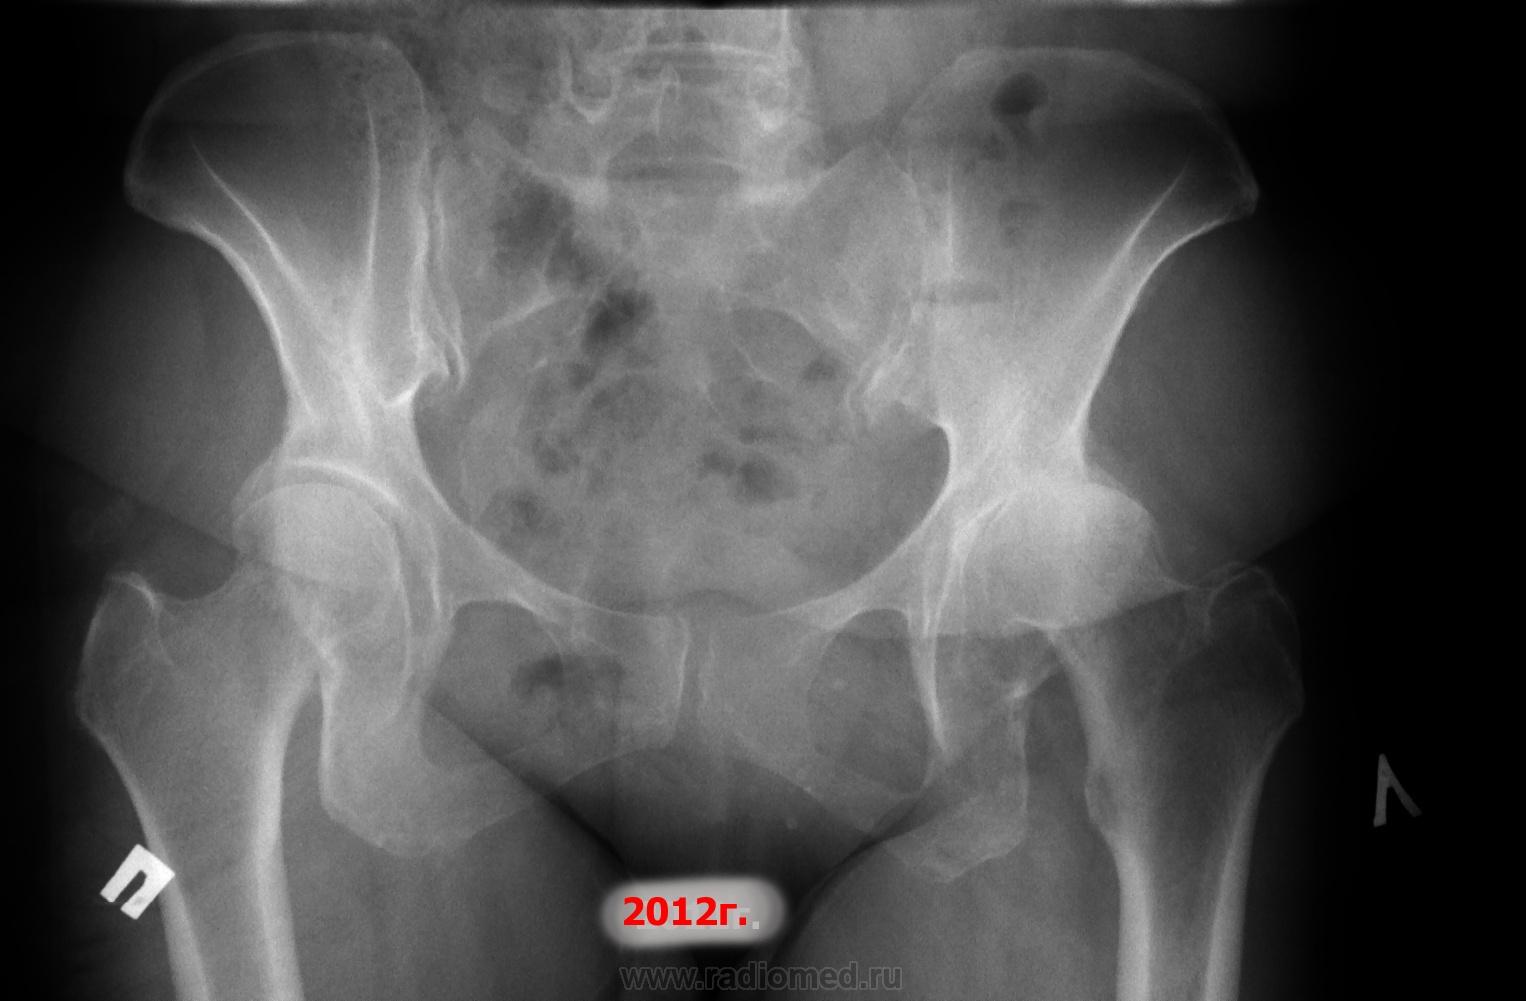

Женщина ,1960г.р., работает, жалобы на боли в суставе, ходит с палочкой, по направлению хирурга: " ДОА слева 3-4?ст, справа -2ст." М.б. всеж ревматоидный? Или асептический некроз? Ну не верится в такое быстрое развитие ДОА... С любым мнением согласен.

В июне 2012г. я писал "ДОА 3ст, не искл. РА". Где и как дальше- нет данных.

При РА суставы поражаются симметрично, в том числе и тазобедренные. При том, что в левом катастрофа, в правом суставе за полтора года без существенной динамики...

Доктор Алкс сказал, что будет согласен с любым мнением. Тогда – онкология на первое место. По порядку: миеломная болезнь, метастазы. Далее - остеосаркома тела подвздошной кости.

Как по мне, второй снимок не является отображением динамики заболевания. На первом суставная щель не прослеживается и контуры суставных поверхностей ровные; на втором снимке и щель появилась, и контуры чего-то стали «изъеденными». Асептический некроз сначала бы съел головку, а потом был бы выраженный артроз, а не наоборот. Картина на первом снимке представляется мне как вторичный артроз на фоне какого-нибудь импинджмента – синдрома (хотя может опухоль уже и была).

Обращает на себя внимание разрушение суставной впадины более, чем уплощение головки. Скоро возможен вывих бедра. Округлое просветление в правой лобковой кости- это газ или мтс? Так же вероятен сростающийся перелом нижней ветви лобковой кости слева.

Артрит в левом ТБС суставе был и в 2012 году. Сейчас выскажусь за асептический некроз. Суставная впадина тоже может страдать. Вот к примеру об этом информация http://bolsustav.ru/asepticheskij-nekroz-golovki-bedrennoj-kosti.html

Лично я был за РА! Вы выразили все за и против. По РА некоторые пробы отрицательные, (срб - белок -). Про вертел- это очень характерно для РА. Но, все мои коллеги за АНГБК.

Ну допустим асептический некроз слева, а справа что ДОА? Да с чего это у женьщины в 53 года нарушения как минимум в 2-х суставах. Асептический некроз если он здесь был, то не являлся самостоятельной нозологической единицей, а являлся как проявления болезни которую нужно найти или попытаться найти. Проще всего сойтись на асептическом некрозе и порекомендовать эндопротезирование, затем поменять и второй сустав и колени и т.д...

Ещё от Рейнберга запомнилось, что некроз кости сопровождается уплотнением её стуктуры, затемнением, а признак артрита - остеопороз, что и имеет место в представленном наблюдении.

Какая на ваш взгляд, стадия у данной пациентки в настояшее время? Не видно ни "секвестрации", ни "репарации", ни (тем более) "вторичного деформирующего артроза". Неужели это все еще стадия "импрессионного перелома"? Тоже нет, и суставная щель не расширена, да и трудно представить, что все остальные стадии еще впереди.

Думается, первый снимок 2-3ст (ретроспективно, конечно). Последний снимок - 5ст. Я обратил внимание на несоответствие суставной щели 2-3ст при первом снимке, должна бы быть расширена. Да только там уже нарушение соотношений, и по одному прямому снимку вряд ли достоверно сможем её оценить. А на последнем - пожалуйста, в динамике, даже при явном подвывихе, она расширяется. Отсутствие репарации в виде какой-никакой головки: так ведь человек избытчного (мягко говоря) веса на всем этом ходит. Да и не нужно забывать, что человеку не 25-40 лет. Трофика и обмен не те. Всё это - имхо, просто высказанное и не навязываемое.

И не мужчина, а женщина. И не 22-45, а 54 года. И щель на начальном этапе не расширена (и даже не нормальная), а уже сужена; и репарации почему-то нет (а лишний вес у 54-летних женщин не исключение, а норма); и 5 стадия - должно быть завершение процесса, а по снимку завершение процесса (мягко говоря) неочевидно.

Может, все-таки (при стольких исключениях), сделать вывод, что это и не асептический некроз.